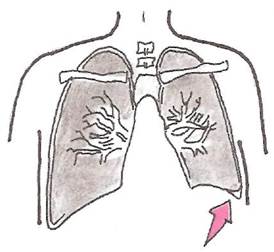

При парапневмонических выпотах средостение смещается в здоровую сторону. При опухолевых плевральных выпотах, сочетающихся с обтурационным ателектазом, который локализуется на стороне выпота, средостение смещается в сторону пораженного легкого (рис. 19).

При правостороннем парапневмоническом плеврите средостение смещается влево. При этом верхушечный толчок может локализоваться на уровне передней аксиллярной линии (рис. 19, а). В этих случаях отмечается выраженная тахикардия до 120-140 в мин, появление акроцианоза и других признаков сердечной недостаточности.

Левосторонний экссудативный плеврит сопровождается смещением правой границы относительной тупости сердца вправо (рис. 19, б). При значительных смещениях средостения вправо может произойти перегиб нижней полой вены в месте перехода ее через диафрагму, в результате чего резко ограничивается венозный возврат крови к сердцу, снижается ударный объем и сердечный выброс, развивается стойкая артериальная гипотензия.

Рис. 19. Смещение средостения при правостороннем (а) и левостороннем (б) плевральном выпоте.